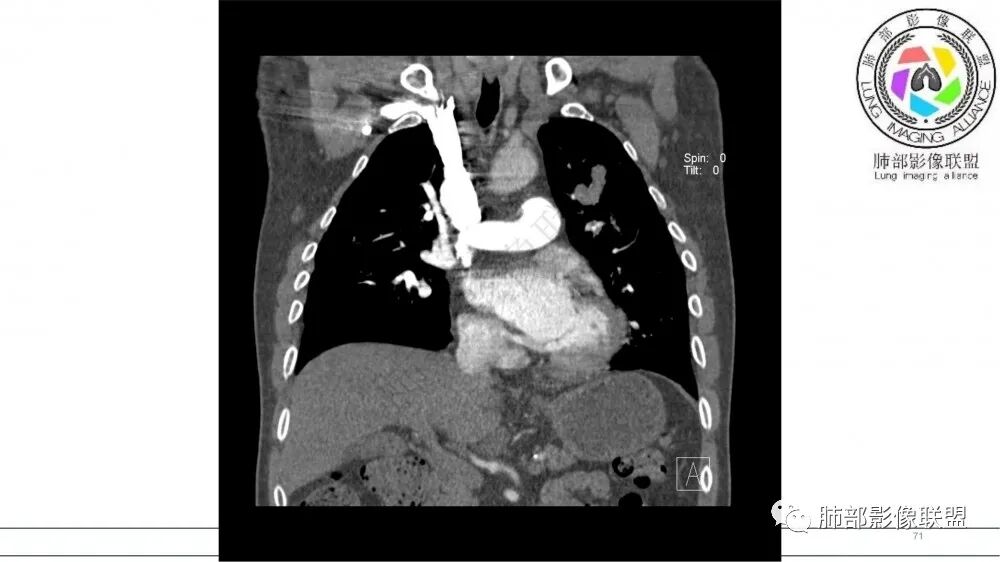

左肺上叶尖后段支气管近端截断,远端见高密度铸型,远侧见阻塞性改变,老年男性,吸烟史,考虑恶性,鳞癌。ABPA代排

指套征,扩张支气管内软组织强化,远侧肺野阻塞性炎,纵隔、左肺门肿大淋巴结;老年男性,吸烟,考虑鳞癌,鉴别小

老年男性,术前检查肺气肿背景,左肺上叶结节,沿支气管蠕虫样生长,左肺门及纵隔淋巴结肿大,增强扫描不均匀强化,血管包绕,结合吸烟史,考虑小细胞肺癌。

指套征:是影像征象,胸部平片表现为手指状密度增高影,以肺门为中心呈放射状分布,CT显示扩张支气管内低密度黏液栓形成或实性病变,呈管状、树枝状或卵圆形密度增高影;支气管扩张伴近端梗阻时,扩张支气管内部黏液分泌物不能排出而形成。可以伴随远端空气潴留征、阻塞性炎症。

研究报道,中心型 SCLC 经 CT 扫描后通常支气管表现为鼠尾样狭窄,肺门或纵隔肿块明显,由于肿块沿管壁生长表现为顺延支气管形态的不规则形状。病灶相对特征性影像学表现比如鸭蹼状、腊肠状、葫芦状及葡萄状改变,可以出现血管包埋,很少有空洞、空泡,较少引发肺不张,阻塞性炎症成都较轻。与一般肺癌比较,恶性程度高,侵袭力强、病灶很小就容易远处转移!Herzberg 等[19]研究指出,20%以上 SCLC 倍增时间短,预后不良。